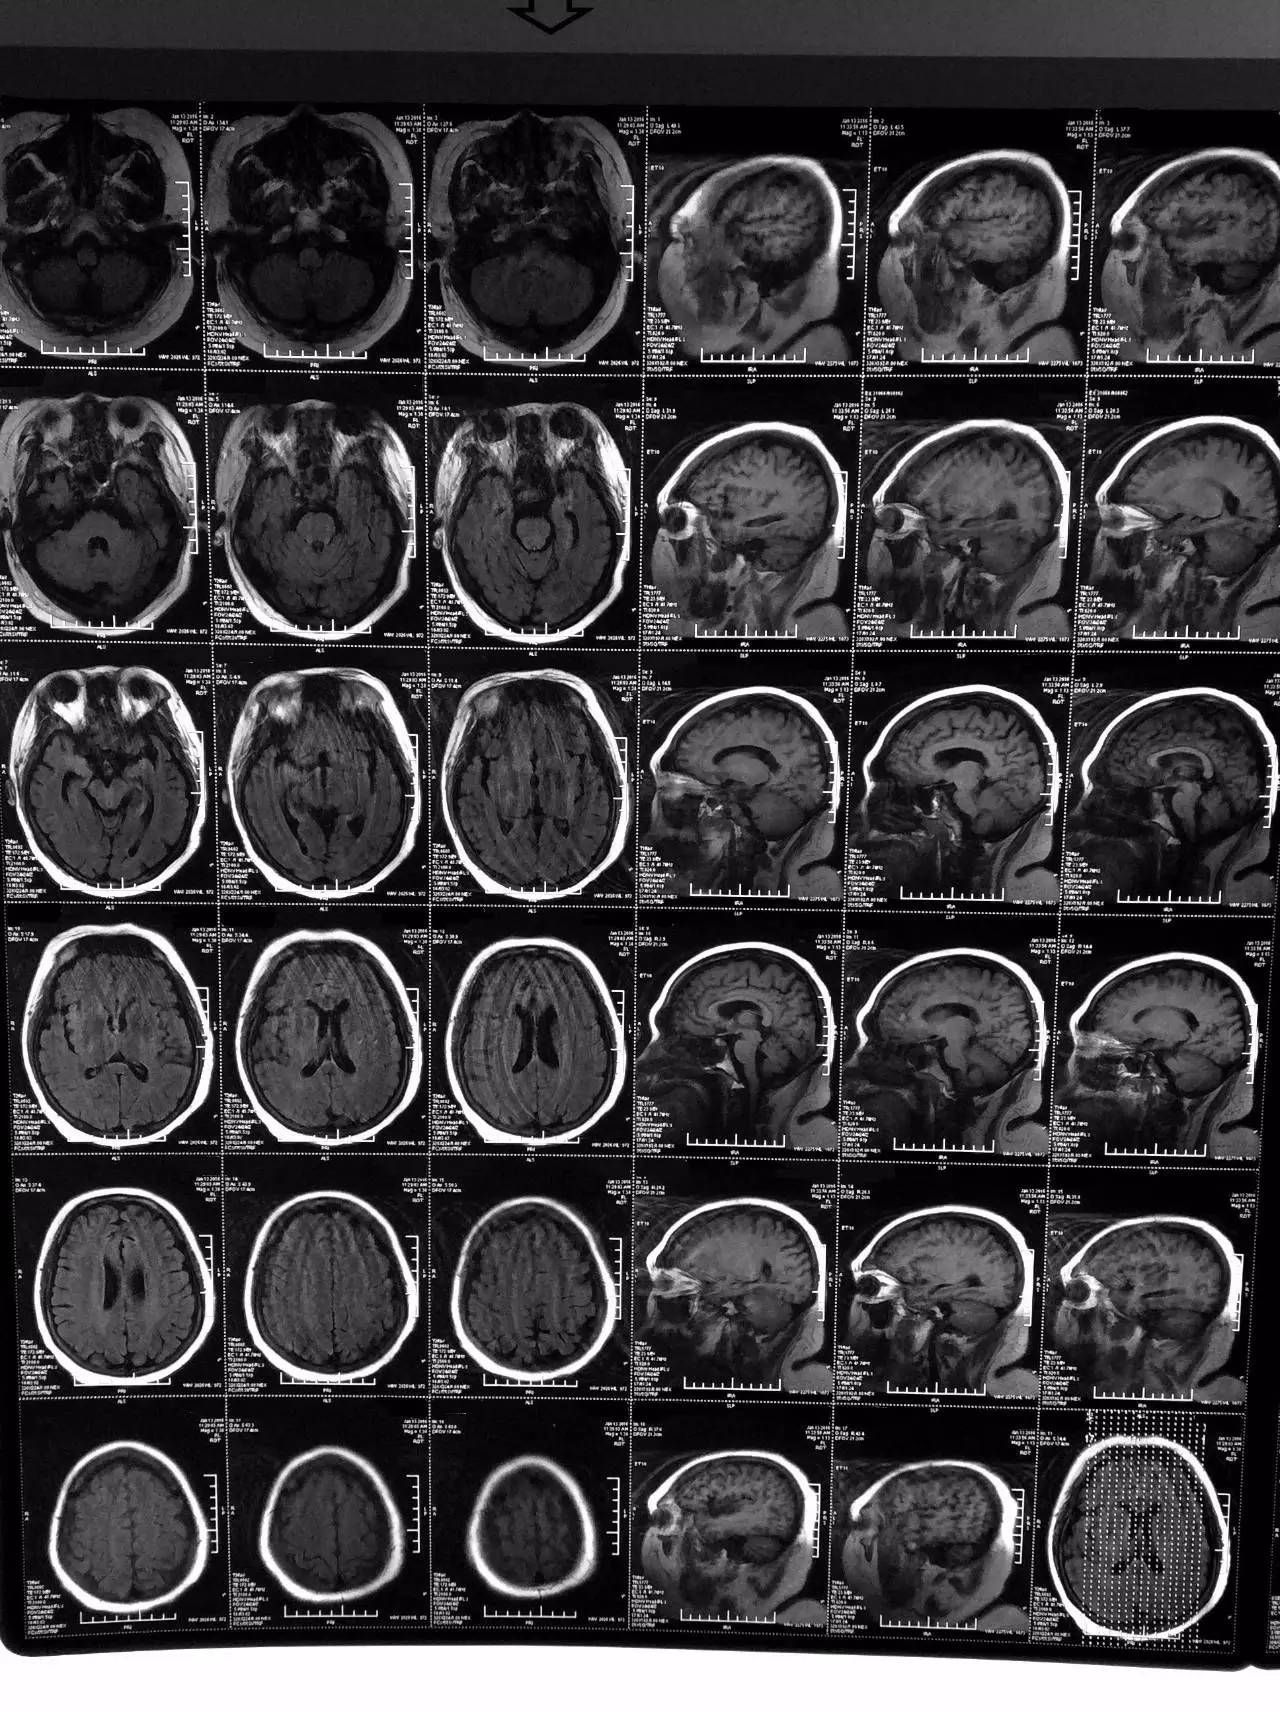

▼患者影像资料